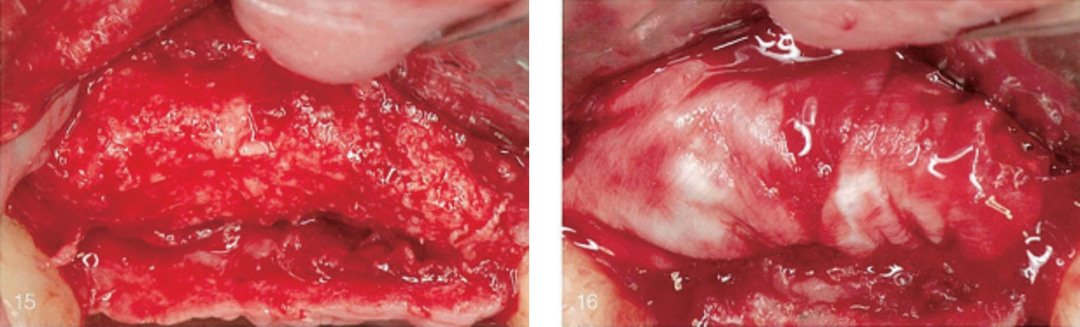

(15)唇侧观, 术区冲洗后 ;(16)唇侧观, 术区放置天然胶原膜。